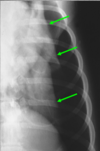

61

“Donuts” and “tram lines”

The radiographic signs of a bronchial pattern are ring-like opacities (“donuts”) and parallel lines (“tram lines”). A bronchial pattern is an abnormal lung opacity caused by peribronchial cellular, fluid and fibrotic infiltration, or bronchial mucosal and submucosal thickening (chronic bronchitis).

Doughnuts and tram lines = bronchial pattern Doughnut sign refers to cross-sectional views of thickened bronchi that appear as circular (or "doughnut"-shaped) opacities, usually seen in conditions where the bronchial walls are thickened. Tram tracks (or tram lines) describe the longitudinal view of thickened bronchi, appearing as parallel lines due to thickened airway walls.

65